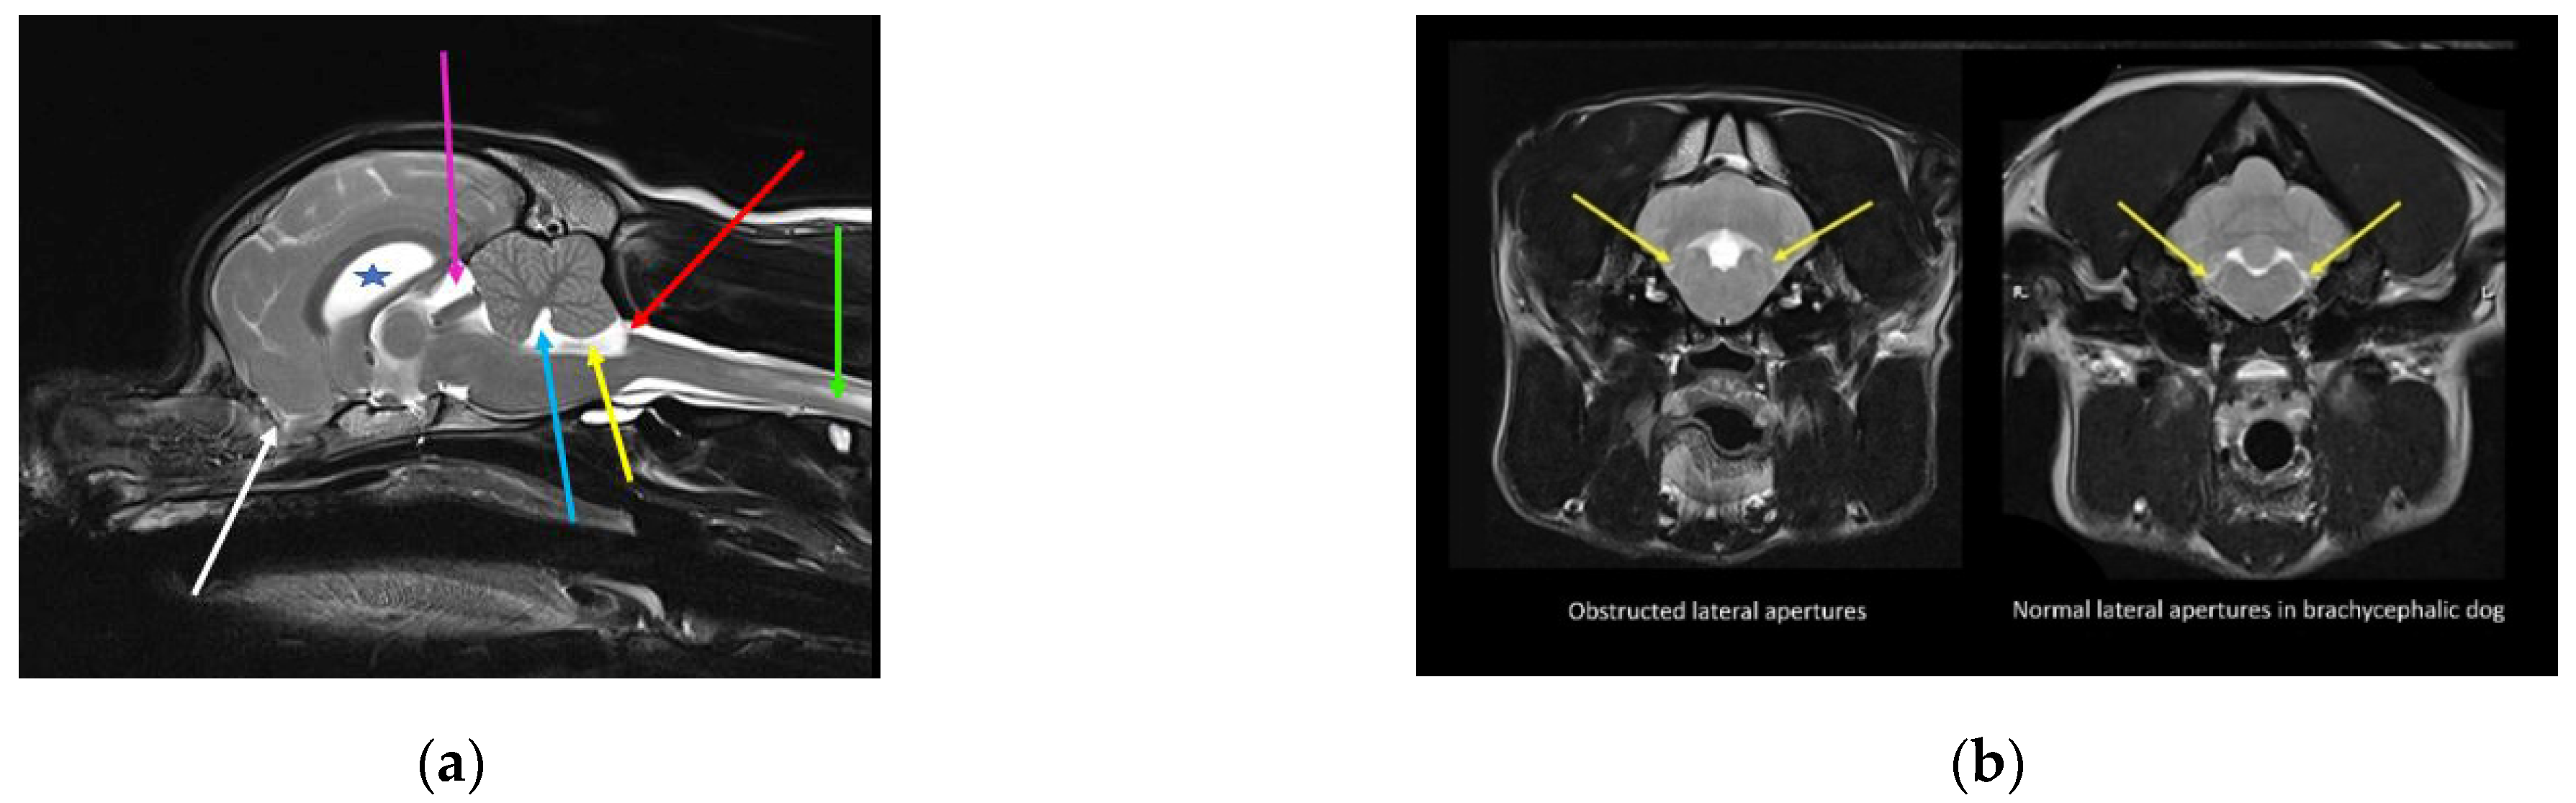

Figure 1.

Skull and craniocervical junction changes with extreme brachycephaly. Reconstructed and midsagittal CT of two female sibling Chihuahuas aged one year old. (a) Less extreme 2.5 kg female Chihuahua, sibling to (b). (b) More extreme miniaturized and brachycephalic 1.6 kg female Chihuahua, sibling to (a). With increasing brachycephaly, the angle of stop (junction between frontal and nasal bones; aqua angle) becomes more acute. With more extreme brachycephaly, ventral brain rotation is more pronounced (orange arrow). There is a relative increase in the cranium height (blue arrow), and the molera (persistent bregmatic fontanelle; purple arrow) is wider. Altered occipital bone conformation changes the angle between the skull base and the cervical vertebrae, resulting in a cervical flexure (red line) and dorsal tipping of the odontoid peg into the spinal cord (white arrow). The oropharynx is displaced caudally (green arrow). There is also a Chiari-like malformation with a small caudal fossa, reduced occipital crest, and a short, more vertical supraoccipital bone (pink arrow). The supraoccipital bone has failed to ossify ventrally. The atlas is closer to the skull, contributing to the craniocervical junction overcrowding (images created by C. Rusbridge and S.P. Knowler).

The skull base forms the lower part of the foramen magnum, which accommodates the craniospinal junction. Premature closure of the spheno-occipital synchondrosis alters the angulation between the skull base and the cervical vertebrae [59,60,61]. The skull base is flexed dorso-caudally, which is mirrored by a corresponding “concertina” brain flexure (so-called sphenoid flexure) [61]. The occipital condyles and the foramen magnum rotate rostrally and ventrally [60]. This craniocervical junction angulation conformation results in ventral deviation of the neck (so-called cervical flexure), with odontoid peg angulation and kinking of the craniospinal junction (Figure 1). This is comparable to basilar invagination in humans. In dogs, this conformation change, in addition to brachycephaly, predisposes syringomyelia secondary to Chiari-like malformation [61,62,63]. Malformation and malalignment of the craniocervical junction can result in obstruction of vascular and CSF pathways [64]. CSF moves caudally from the cranium into the spinal compartment, and is absorbed, together with CSF produced by the spinal cord, by lymphatics in the sacral spine and along nerve root sleeves in the cervical region [26,52]. CSF also moves rostrally from the spinal into the cranial compartment during deep inhalation [50,53] and diastole [52]. It is proposed that dissociation of CSF flow in the cranial and spinal compartments predisposes syringomyelia [65,66].